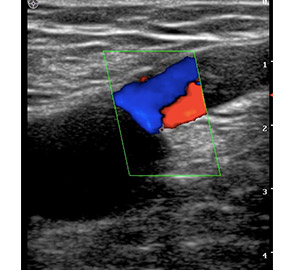

靜脈曲張診斷的正確性非常重要,影響到病人療效的結果與復發率。診斷錯誤或不完整,會造成疾病無法改善或治療後復發機率增高,醫師會透過病史、理學檢查了解病人疾病形成可能的原因,藉由超音波檢查評估後,會對於治療做正確的選擇,正確地找出問題根源所在,才能徹底治療靜脈曲張。